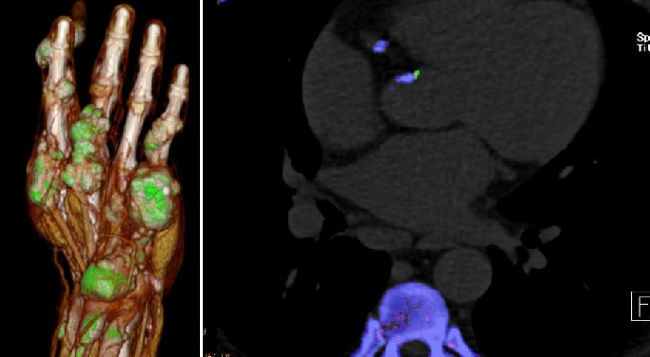

- Dual-energy CT (DECT) in gout: comparison with US, findings in extra-articular regions and cardio in gout and subgroup patients

- X-ray in comparison with DECT in gout patients

- Klauser AS, Halpern EJ, Strobl S, Gruber J, Feuchtner G, Bellmann-Weiler R, Weiss G, Stofferin H, Jaschke W.: Dual-Energy Computed Tomography Detection of Cardiovascular Monosodium Urate Deposits in Patients With Gout. JAMA Cardiol. 2019 Oct 1;4(10):1019-1028.

- Strobl S, Kremser C, Taljanovic M, Gruber J, Stofferin H, Bellmann-Weiler R, Klauser AS.: Impact of Dual-Energy CT Postprocessing Protocol for the Detection of Gouty Arthritis and Quantification of Tophi in Patients Presenting With Podagra: Comparison With Ultrasound. AJR Am J Roentgenol. 2019 Dec;213(6):1315-1323.